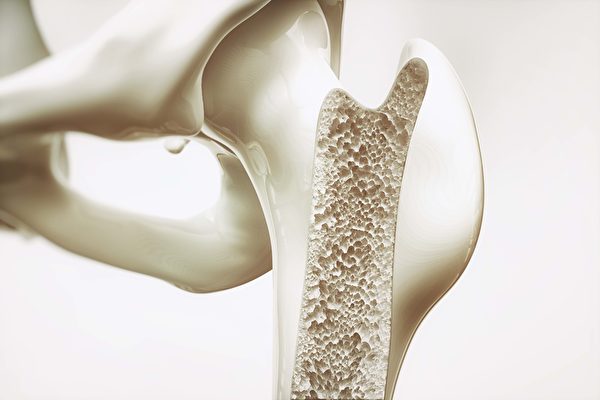

【大紀元2019年12月02日訊】(大紀元記者李少維編譯)人們以為骨骼縱向的板狀結構為骨骼的堅固性提供重要支撐,美國康奈爾大學(Cornell University)一項研究發現,人體骨骼中一些以前以為是裝飾作用的橫向結構對骨骼的耐受程度起到重要的作用。

骨骼縱向的板狀結構決定其強度,人們從未注意過骨骼中的一些橫向竿狀結構,還以為它們只是擺設。這份研究三維打印出這些橫向結構進行耐用度實驗,發現這些竿狀結構的粗細程度可將材料的耐用度提升百倍。